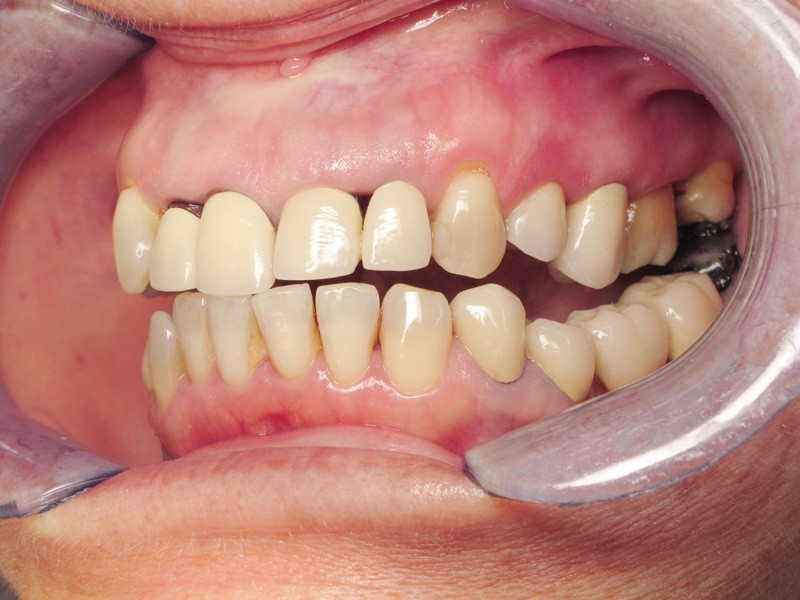

Madame J., âgée de 63 ans, consulte pour des douleurs chroniques localisées au niveau de 14 et de 21. L’examen endobuccal révèle la présence de prothèses anciennes, de soins conservateurs et d’un implant posé depuis 4 ans. On note une inflammation généralisée du parodonte superficiel avec présence de plaque et de tartre et une mobilité de certaines dents dont les incisives maxillaires droites. Dès ce stade, le surguidage antérieur du couple 11/12, reconstitué par des couronnes solidarisées, est à mettre en relation avec la souffrance parodontale observée (fig. 1).

Une inflammation de la zone péri-implantaire (24), en relation avec le motif de la consultation est également visible dès ce premier examen.